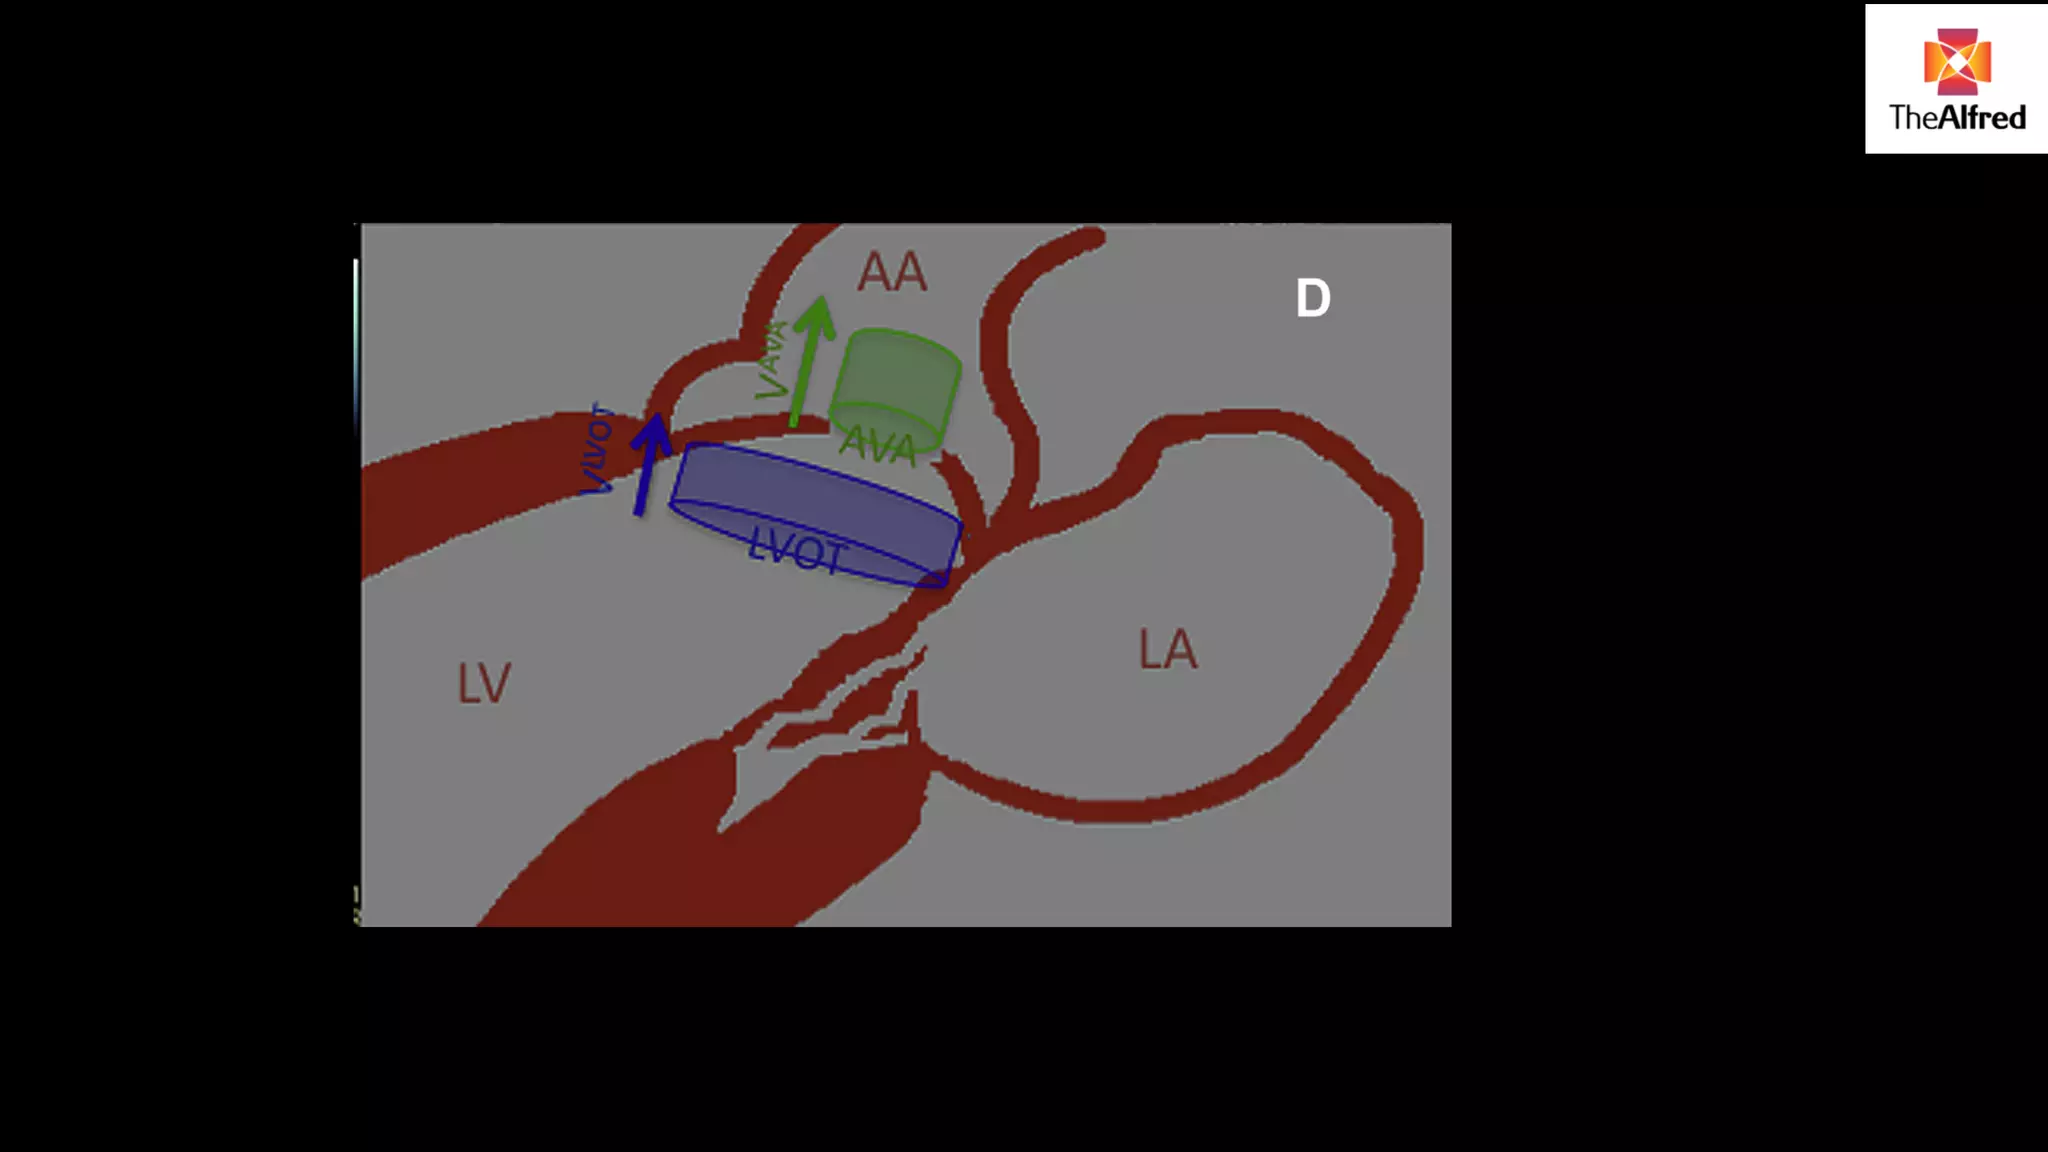

LVOT method

Assumes the LVOT is a cylinder

We can measure the VTI of blood flow in the LVOT by

placing a pulse wave doppler gate in LVOT

This gives us the LVOT VTI

LVOT method Assumesthe LVOT is a cylinder We can measure the VTI of blood flow in the LVOT by placing a pulse wave doppler gate in LVOT This gives us the LVOT VTI

MATHS… Volume =CSAX height (distance) ! Stroke volume= π r2 X VTI ! Cardiac output= SV x heart rate

any measurement errorwill be squared ! CSA= π r2